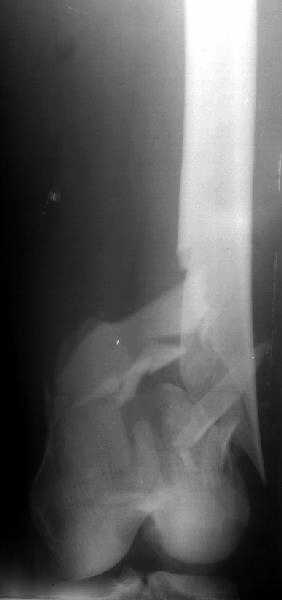

Sorry but I've just prepared postop images - attached. A solid 13 mm nail was used. A few degrees of recurvation appears to be which i missed on image intensifier. I'm still uncertain about

The antegrade nail in the case shown is probably into the knee joint slightly.

TAC> The antegrade nail in the case shown is probably into the knee joint slightly.

Not in this case. Though i have a couple of similar cases with 3-4 mm prominince of the nail - looks asymptomatic or covered by pre-existing problems.